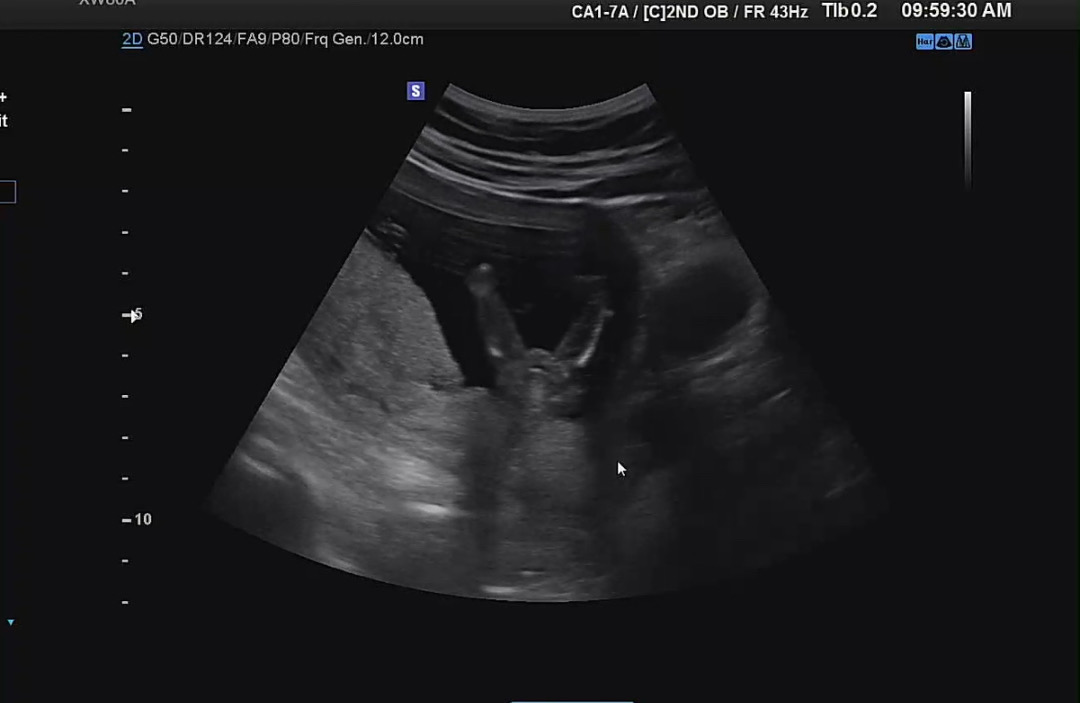

저 딸맘 당첨일까요?

태몽도 입덧도 사주도 다 아들이랬어서 아들이라 생각하고 있었는데 애가 많이 움직여서 잘 모르겠지만 딸 같다고 하셔서 뭔가 충격이네용 혹시 15주 이후에도 성별 반전 있으셨던분 있으신가요?

딸은 20주는 되어야 확정이라고할수있대요 ㅎㅎ 그 이전에는 반전이 하도 많아서 100% 확신은 못하고 90% 뭐 이런다고 ㅎㅎ